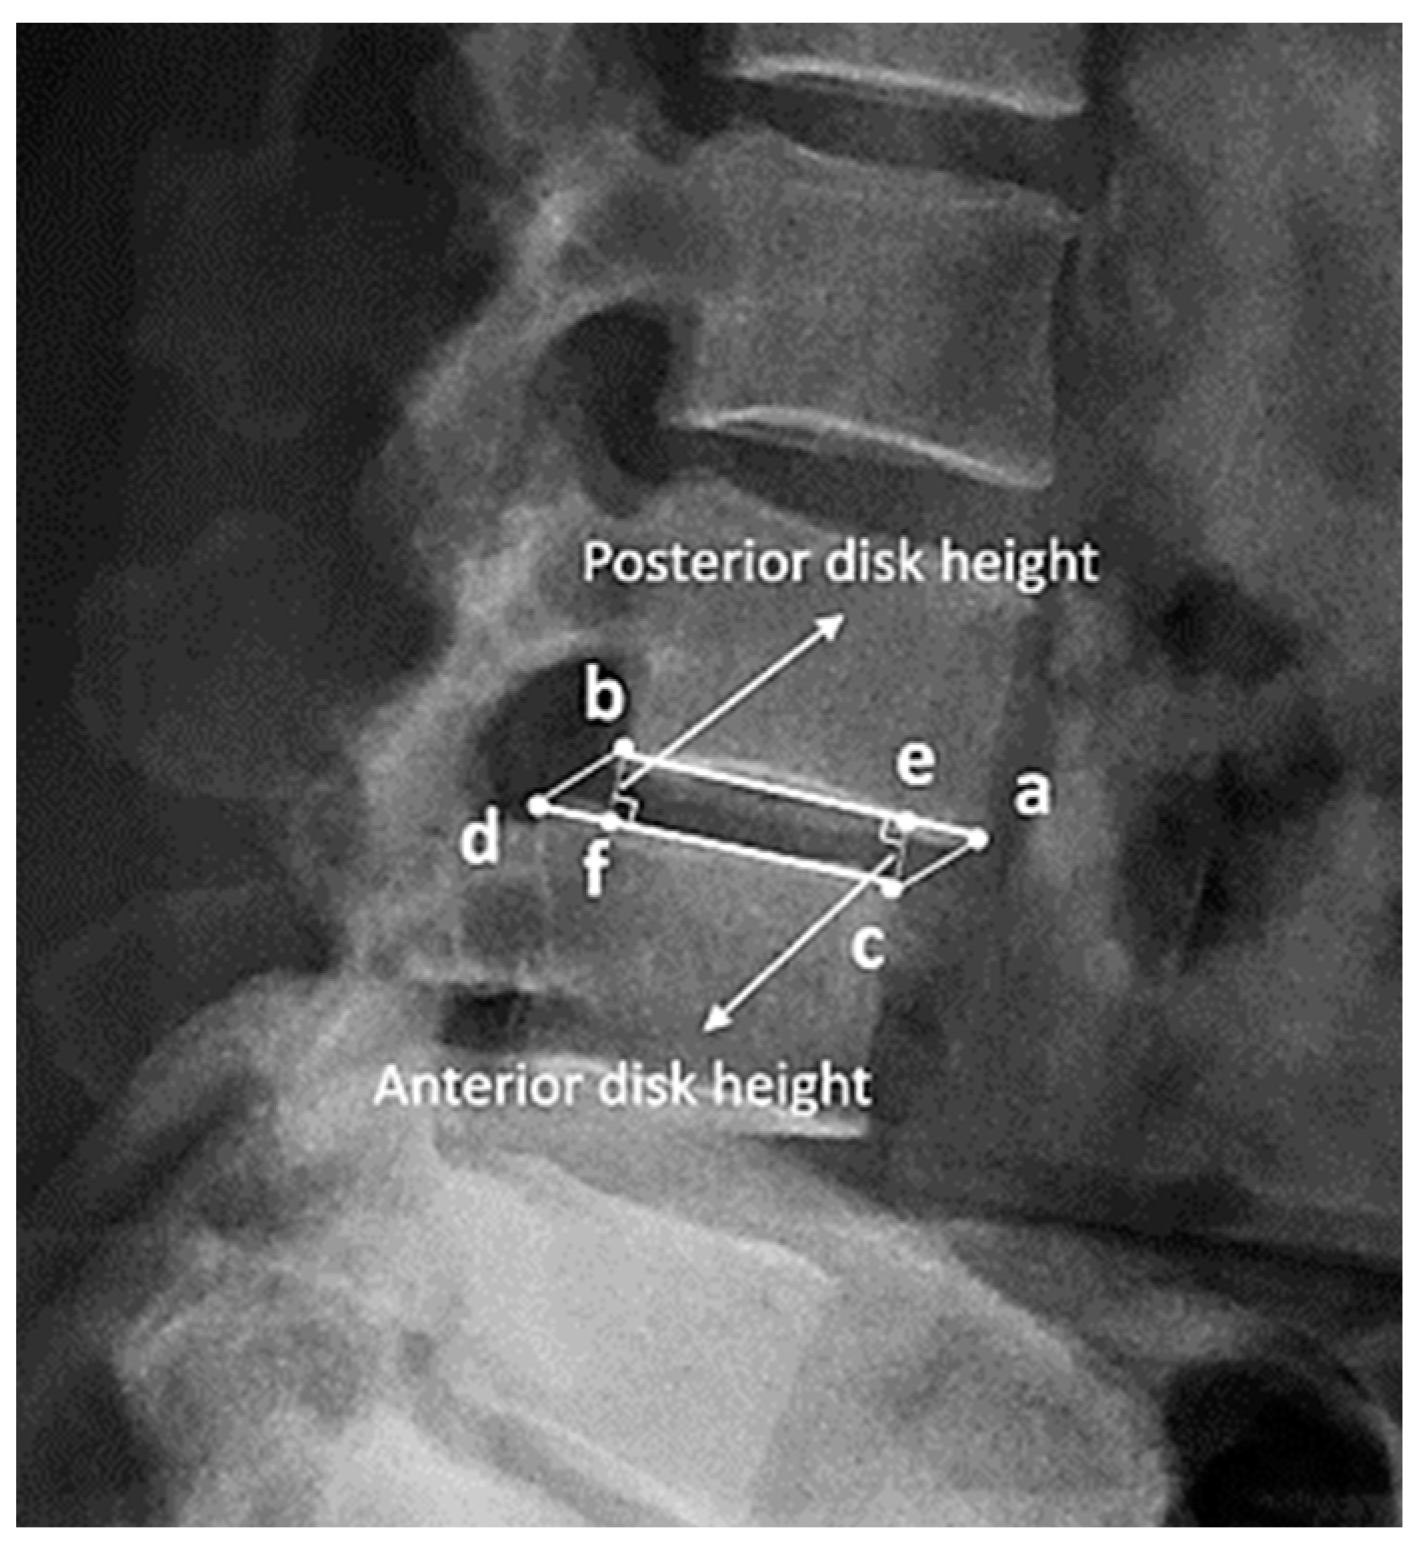

2.3. Definition and Measurement of Disc Height

Measurement of Disc Height with BiLuNet